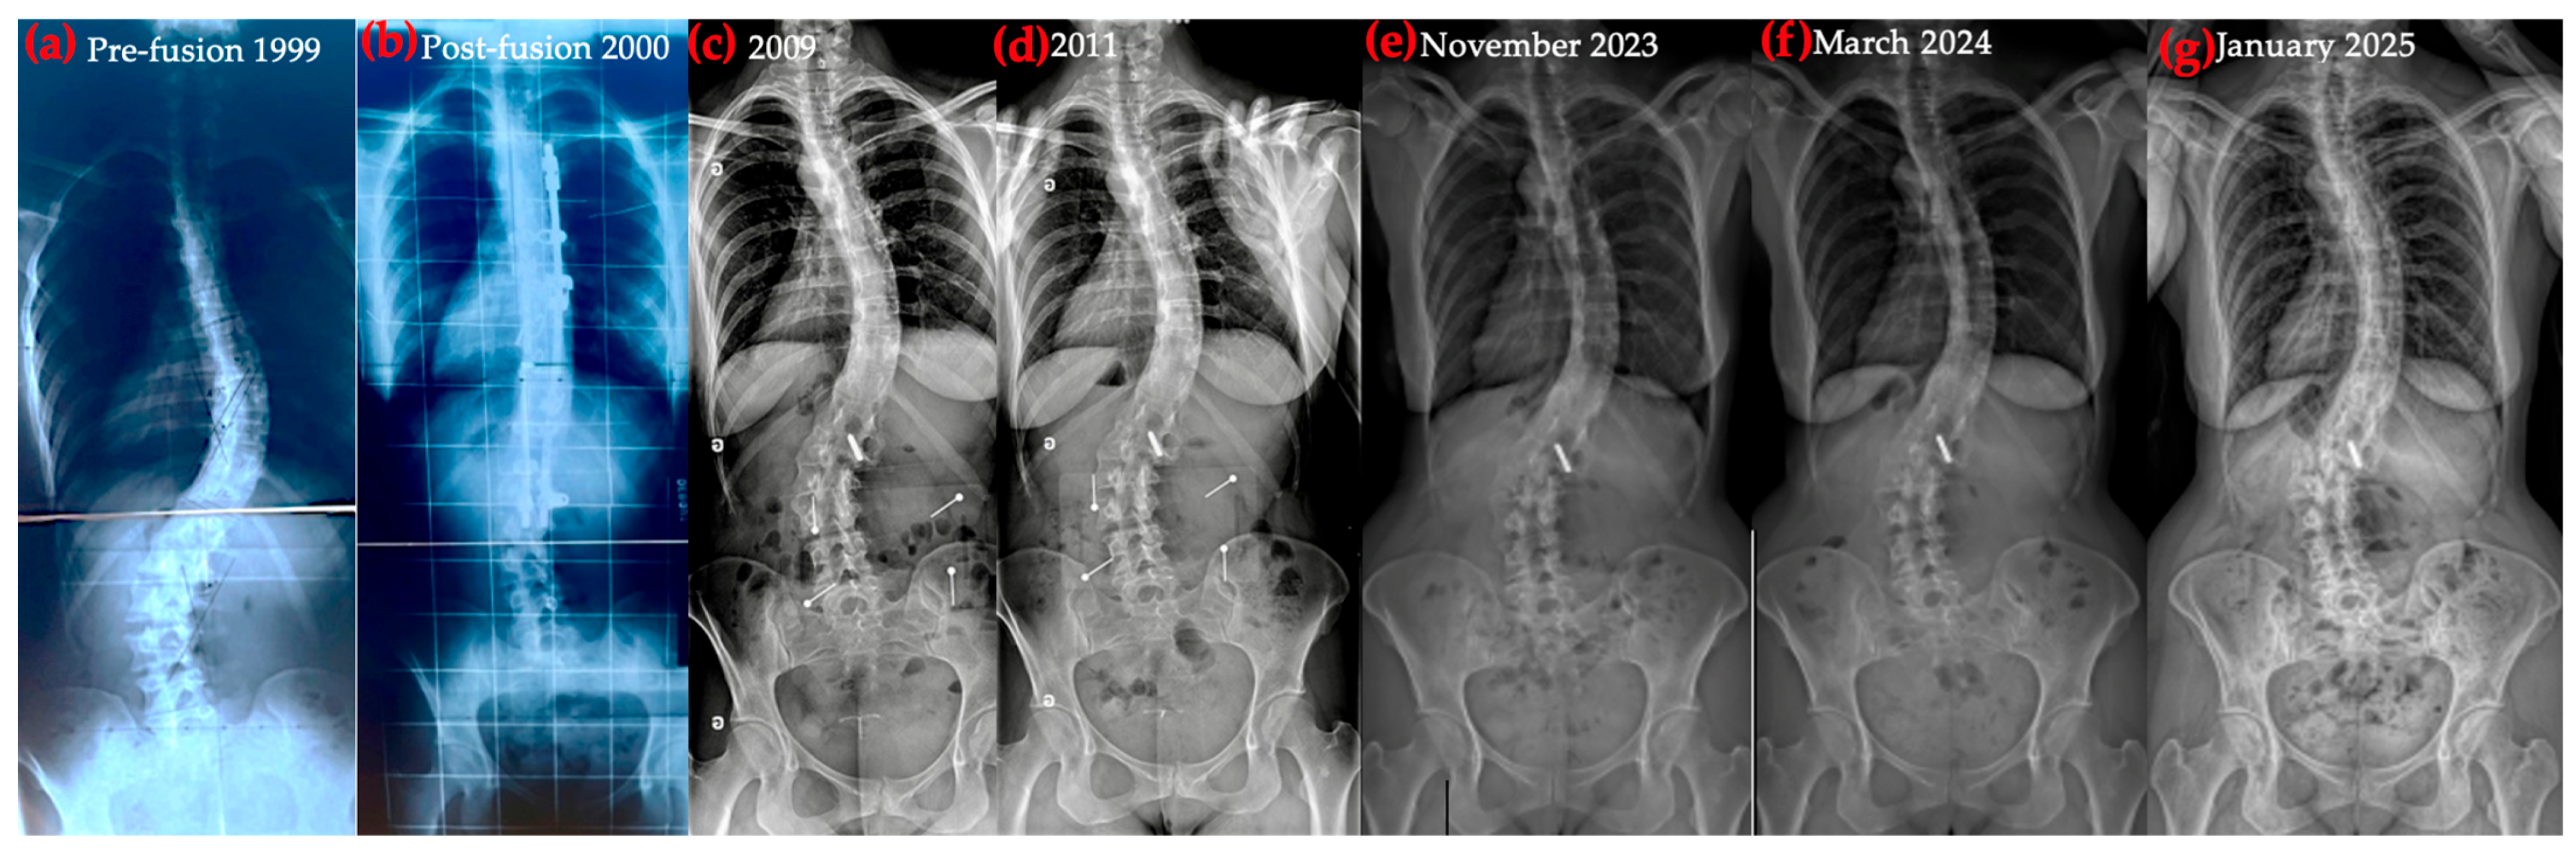

2.1. Initial Diagnosis and Early Management

2.2. Curve Progression and First Surgical Intervention

2.3. Post-Operative Complications and Hardware Removal

2.4. Progressive Postural Collapse Following Hardware Removal

2.5. Baseline Structural and Functional Status Prior to Schroth-Based Physiotherapy